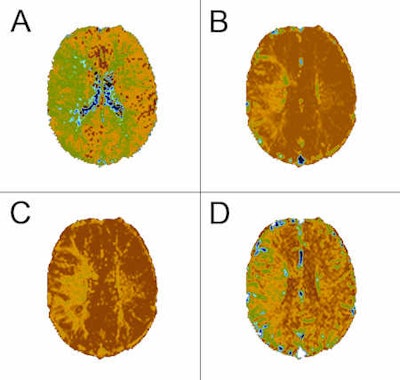

Perfusion imaging is proving increasingly useful for analyzing the biological behavior of central nervous system diseases, particularly the hemodynamic features. Qualitative and quantitative information can now be acquired for evaluating pathoanatomical structures, and pathophysiological changes of the lesions.

The term "perfusion imaging" is extensively used, but is in fact a misnomer because perfusion and blood flow are not the only imaging biomarkers of microvascular structure and function in common use, commented Dr. Alan Jackson, from the Division of Imaging Science and Biomedical Engineering at the University of Manchester, U.K. Indeed, in oncological applications, measurements of proportional blood volume, endothelial capillary permeability, or vessel size can be of equal or greater importance.

At Sunday's session, he was slated to review the biological rationale for using perfusion imaging in brain tumors, the methods available for the imaging of microvascular structure and function in brain tumors, and the methods for dynamic contrast-enhanced imaging and its analysis. He also intended to discuss the clinical applications, focusing on distinguishing abscess from tumor, differentiating tumor types, distinguishing glioblastoma from solitary metastases, and predicting grade, histological subtype, and prognosis in glioblastoma. He was also supposed to look at monitoring radiotherapy and predicting radiotherapy response, as well as applications in clinical trials of novel therapeutic agents, particularly antiangiogenic agents.